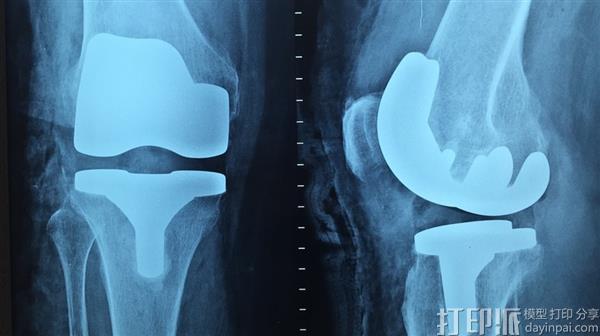

法国最近宣布的一项新的3D打印项目有可能改善世界各地千百万患有膝盖问题的人们的生活。 该项目被称为FollowKnee,由法国国家研究机构(ANR)提供资金支持,并将借助3D打印技术,看到先进的假肢膝关节的发展。 这项多学科合作项目资助了790万欧元的资助,这个项目可能会在未来五年内革新膝盖手术。'

FollowKnee位于该国西北部的布雷斯特市,是一个“联合”这个词的多种意义上的共同努力,因为它涉及七个不同的组织和机构的参与,以及专注于开发替代品膝关节。膝盖是身体的一部分,一生中经受了很多的压力,越来越多的患者现在需要手术和修复术。

FollowKnee的新方法将利用三维扫描和印刷技术,以创建一个更好的人造膝关节设计和开发一种新的方法来生产。该项目还将实施其他尖端技术来处理影响替换手术,假肢装置和病人恢复过程的任何问题。 3D打印将由雷恩公司的SLS公司进行,该公司生产陶瓷牙科配件。 3D印刷的人造膝关节将由陶瓷 - 金属合金制成。

最初,在该计划的头三年,由FollowKnee的外科医生团队安装了220个3D打印假肢膝关节。 他们还将安装大约30个专用传感器,这些专用传感器用于追踪假体的状况并检测出任何问题。 由法国原子能委员会法国格勒诺布尔制造,这些传感器将主要安装在年轻患者身上,因此可以长时间记录他们的表现。 五年后,我们的目标是要有一个市场化的产品已获得临床认证。 Imascap将负责营销工作,以及创建3D模型和维护相关的数据库。